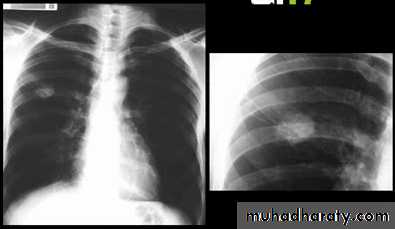

Miliary Tuberculosis. A cone-down view of a frontal radiograph demonstrates innumerable micronodular opacities characteristic of micronodular (miliary)

interstitial disease.

Transbronchial biopsy demonstrated caseating granulomas containing acid-fast bacilli.

Miliary TB

a frontal radiograph demonstrates innumerable micronodular opacities characteristic of micronodular (miliary) interstitial disease. Transbronchial biopsy demonstrated caseating granulomas containing acid-fast bacilli.Tuberculoma